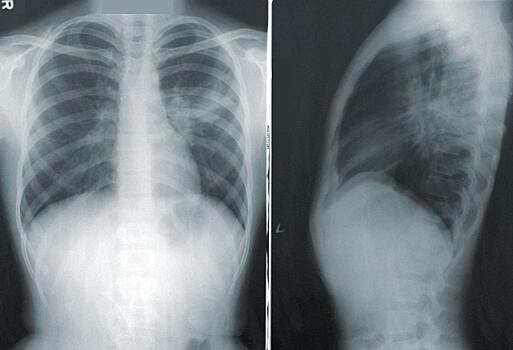

В сулчае, если человек ниак не может отказаться от курения, доктор посоветовал ежегодно проходить обследование и делать флюорографию или рентгенографию легких.